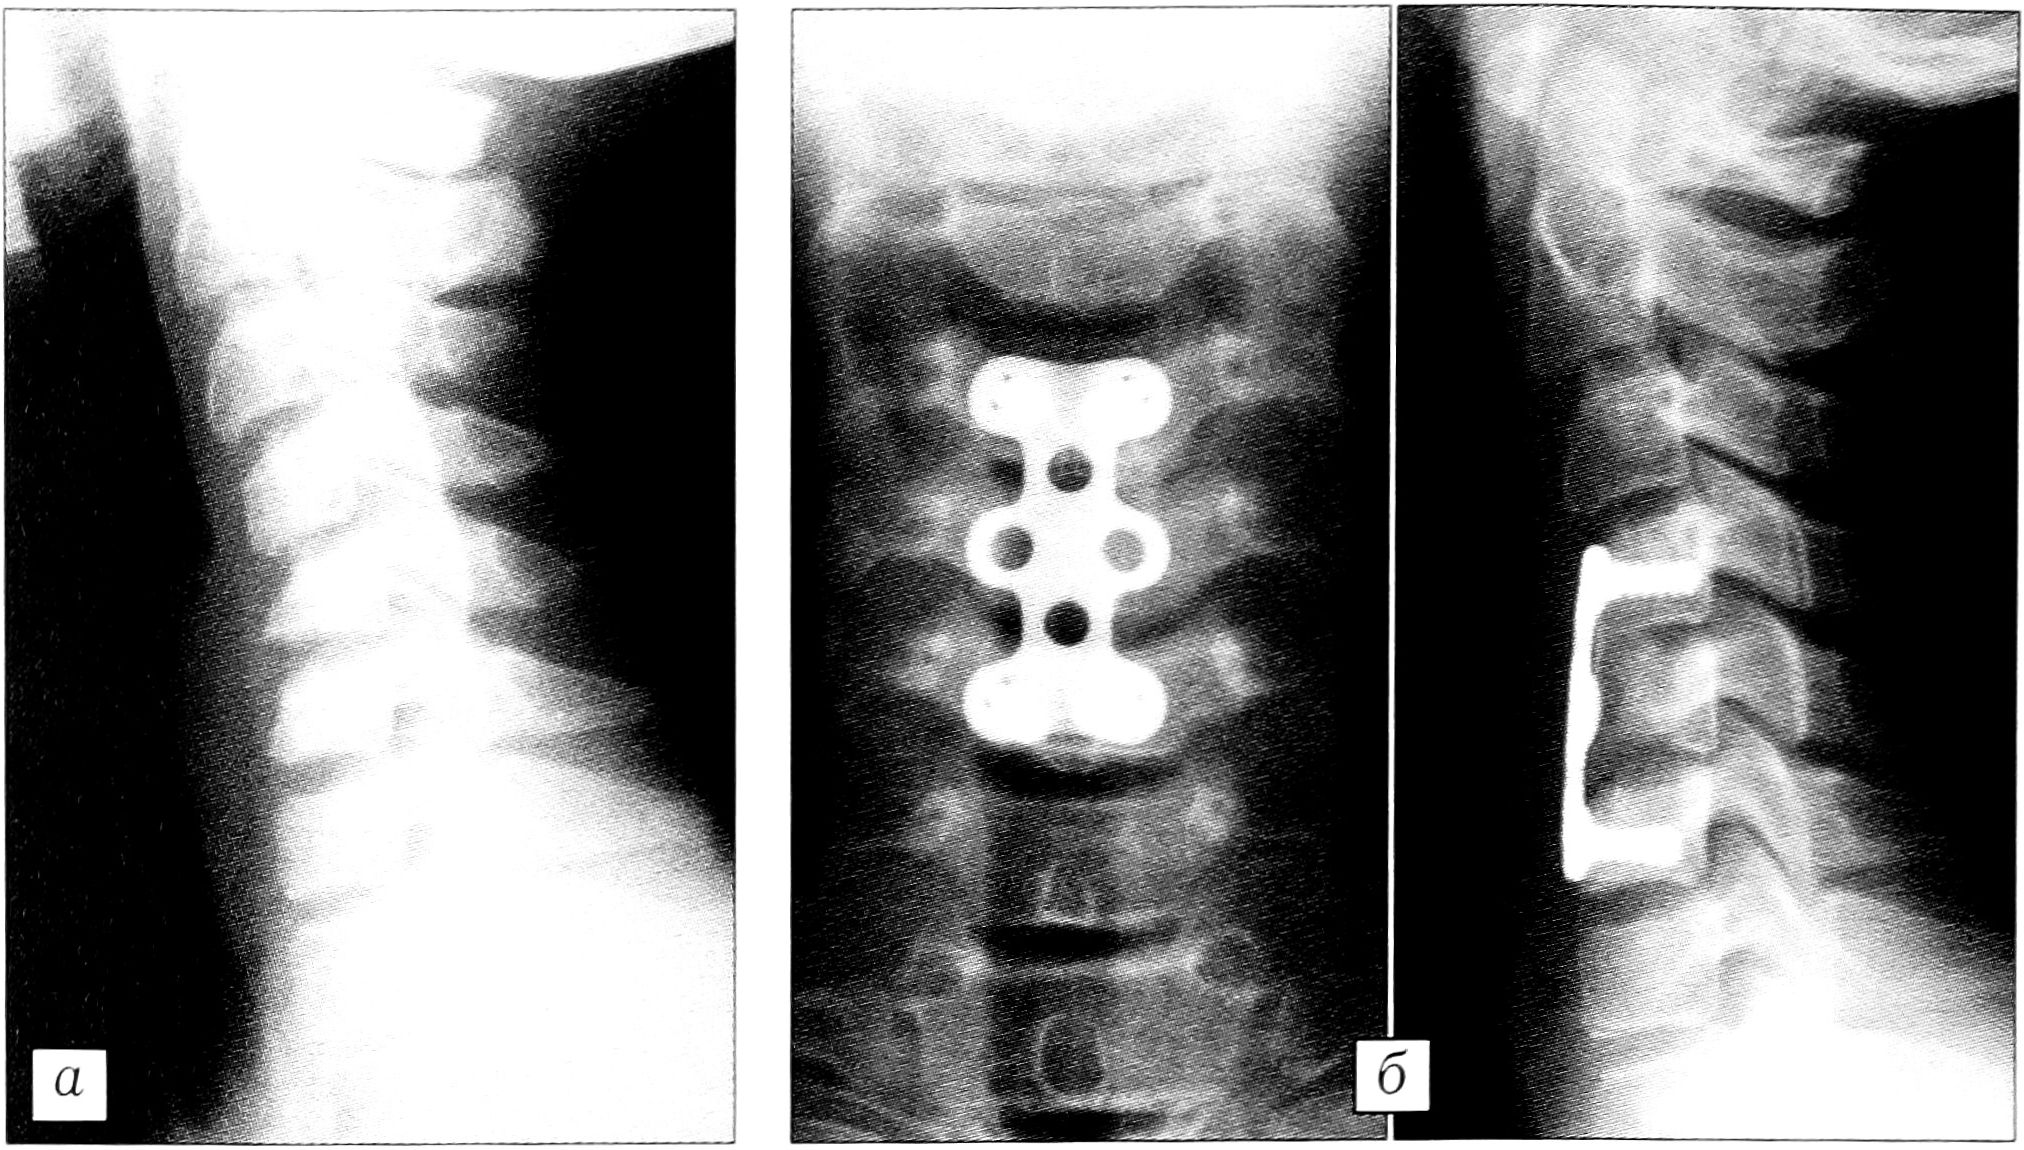

Широко применяя эту систему для фиксации позвонков (табл. 1), мы убедились в значительных ее преимуществах при лечении неосложненной и осложненной травм шейного отдела позвоночника (рис. 1). Ни в одном случае мы не наблюдали миграции пластины или винтов. Все пациенты были активизированы сразу после операции в мягком воротнике, а после заживления раны — без внешнего фиксатора. Необходимо подчеркнуть, что все это возможно только при тщательном соблюдении технологии фиксации.

Рис.1. Больной Е. 16 лет. а — рентгенограмма при поступлении: компрессионный осложненный перелом С 5 позвонка; б — рентгенограммы после операции: передняя декомпрессия, спондилодез С4-6, фиксация СSLР.